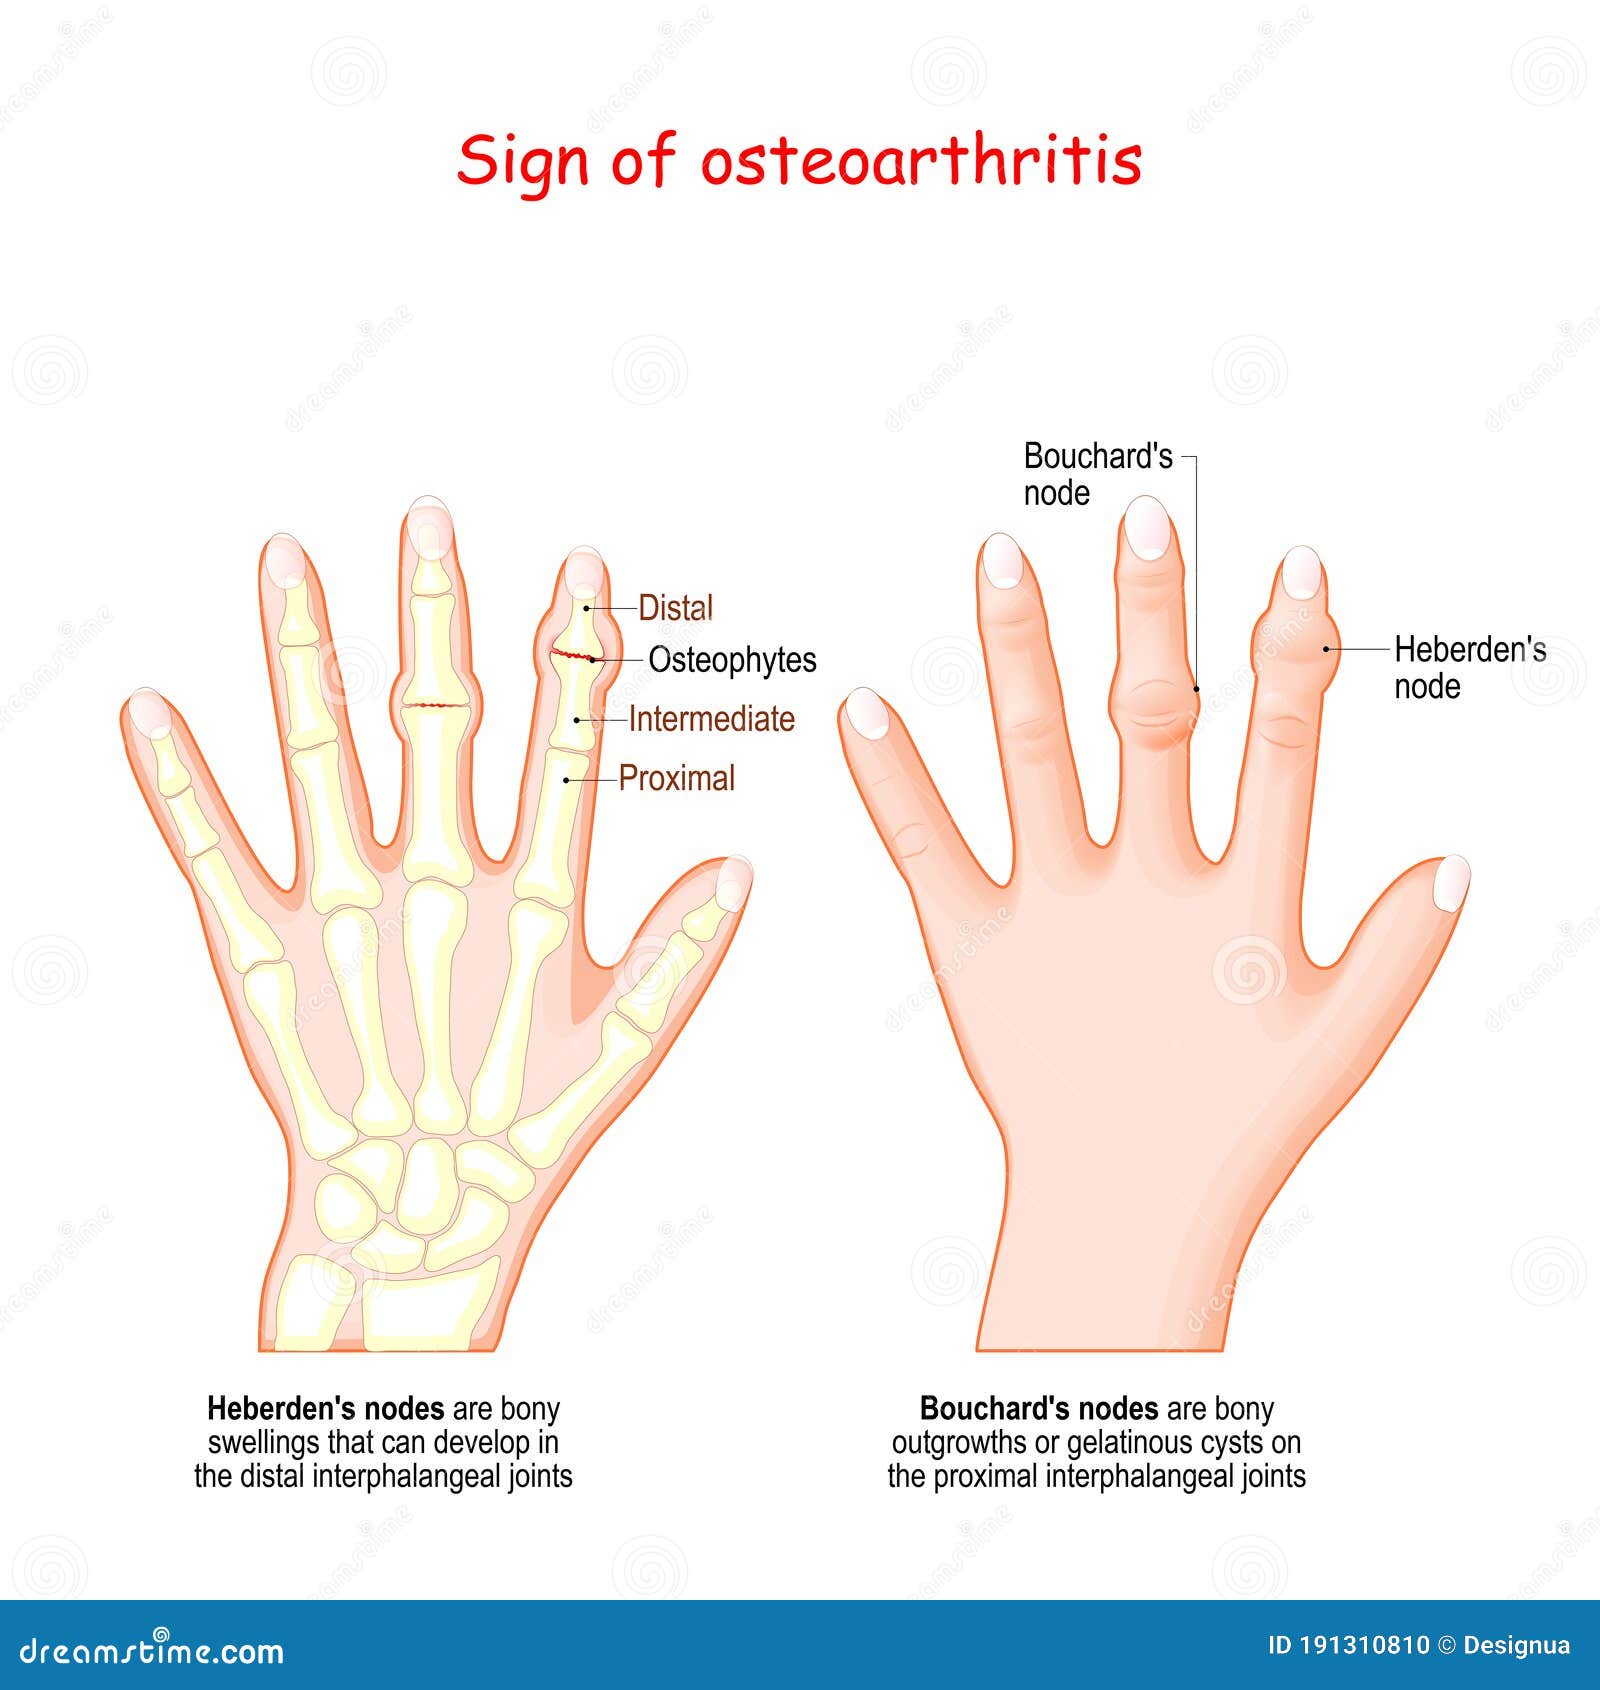

Heberden S Nodes In Osteoarthritis And Rheumatoid Arthritis

Heberden S Nodes In Osteoarthritis And Rheumatoid Arthritis

Bouchard Clipart And Illustrations

Rheumatoid Arthritis Vs Osteoarthritis Keri Leigh Biomedical Creations

Bouchard Nodes What Are They Causes Signs Symptoms And More